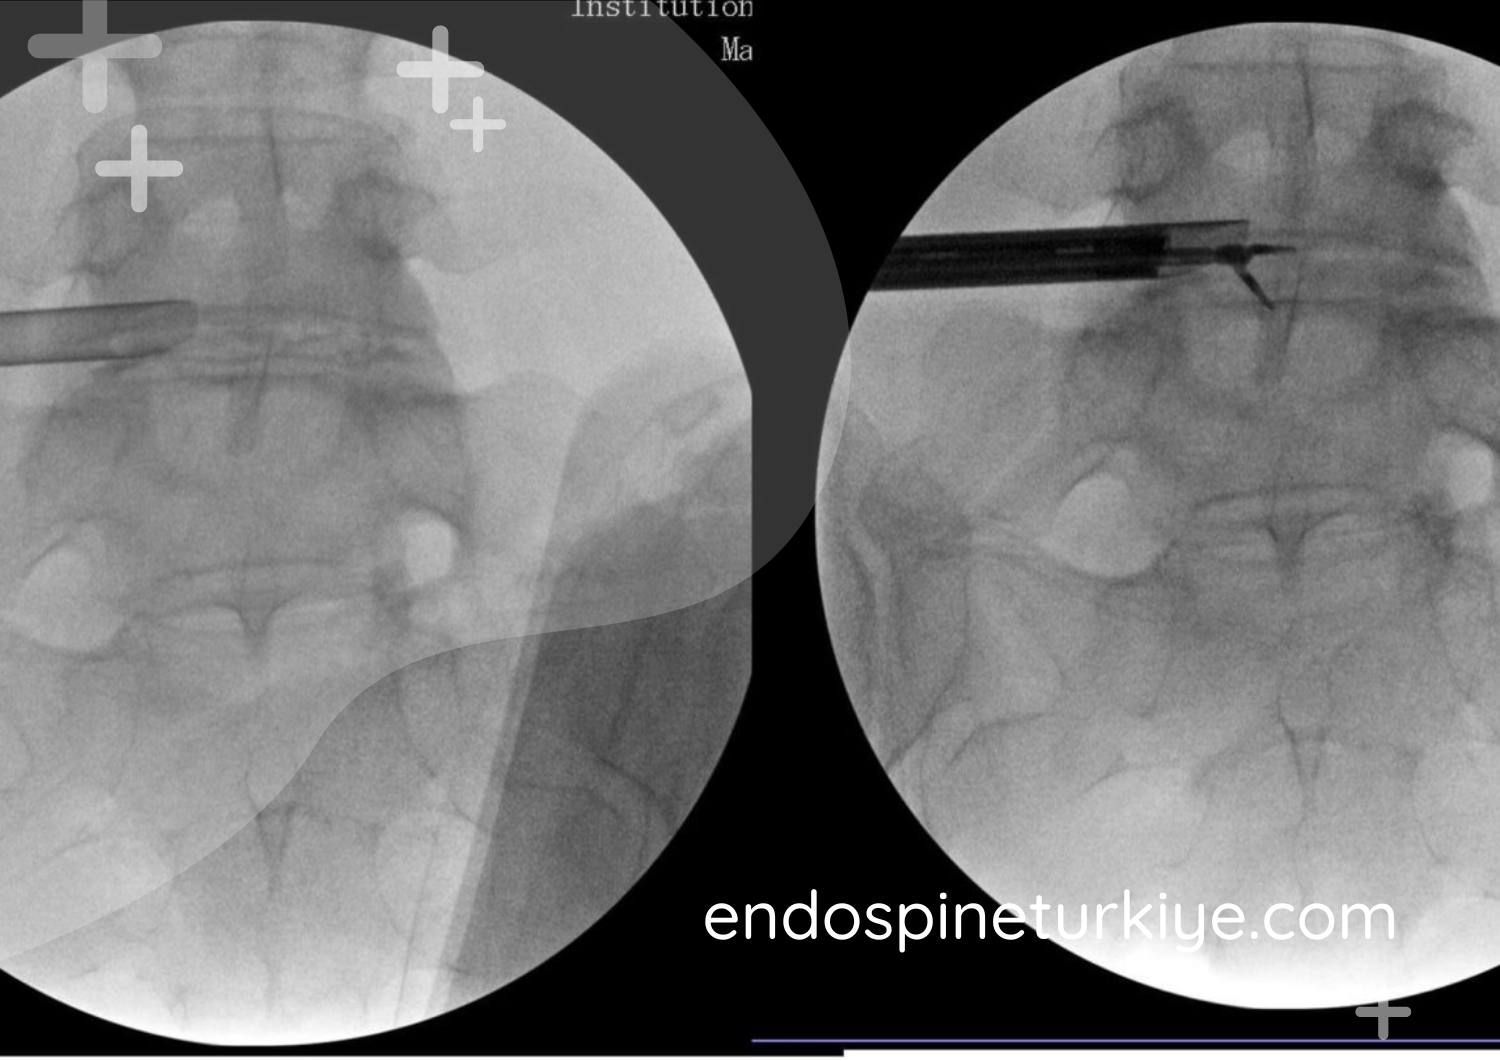

Tam kapalı endoskopik bel fıtığı ameliyatı görüntüsü - 6mm kesi ile minimal invaziv cerrahi işlem, HD endoskop kullanımı

Tam kapalı endoskopik bel fıtığı ameliyatı, günümüzün en modern ve minimal invaziv omurga cerrahisi tekniğidir. Bu yöntemde, sadece 6mm'lik bir kesi ile endoskopik kamera ve özel cerrahi aletler kullanılarak fıtık dokusu çıkarılır. Perkütan endoskopik lomber diskektomi (PELD) olarak da bilinen bu teknik, klasik mikrocerrahi yöntemlere göre çok daha az invazivdir.

Endoskopik Görüntüleme

HD kamera ile fıtık dokusu net görüntülenir